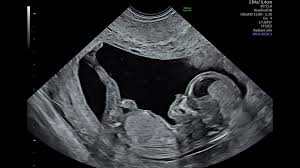

It was during one of those routine ultrasound visits that something unexpected appeared on the screen.

Amanda’s youngest daughter, Bailey, had accompanied her to the appointment. As the image flickered into view, Bailey pointed at the screen and asked a simple but startling question: whose hand was that?

The black-and-white ultrasound image seemed to show a large hand-shaped figure cradling the baby’s head. To Amanda, the image felt unmistakable.

She later wrote that the sight overwhelmed her with emotion, bringing her to tears. For her, the image symbolized protection, reassurance, and a reminder of God’s presence during her most fearful moments.

What others might see as a visual coincidence, Amanda experienced as deeply personal and spiritual — a moment that restored faith shaken by years of uncertainty and loss.